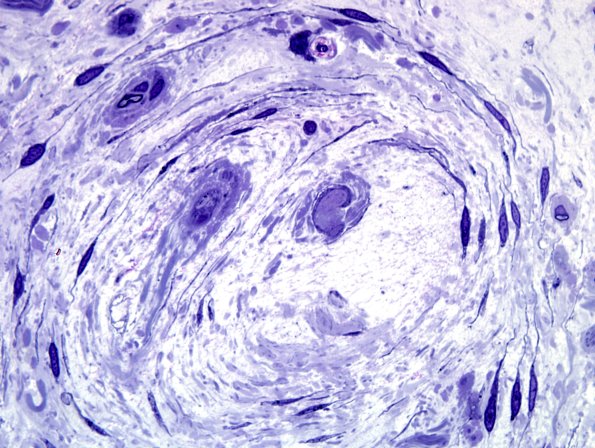

8 Renaut bodies

5F10 Renaut body-oma (Case 5) Plastic 100X 26.jpg

Additional Renaut body. (Plastic section)